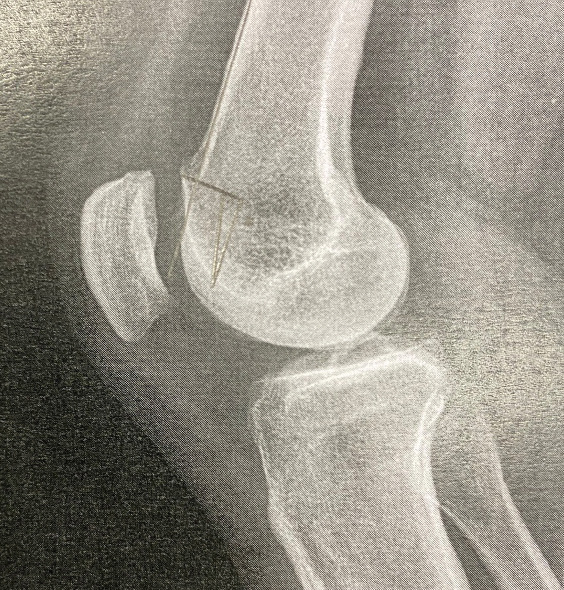

简介:屈曲期间的慢性髌骨脱位是一种罕见的与股骨发育不良和动态髌骨畸形相关的疾病。股前肿块的存在导致了机械冲突。病例报告:我们报告一例年轻成人慢性髌骨脱位膝关节屈曲期间,与髌股发育不良,前隆起,和外侧松弛。结论:治疗方法为股前远端减截骨联合髌股内侧韧带重建。术前和术后的文献资料以及影像学证实了不稳定性的矫正。

Introduction: Chronic patellar dislocation during flexion is a rare condition associated with femoral dysplasia and dynamic patellar maltracking. The presence of an anterior femoral bump contributes to the mechanical conflict.

Case report: We report the case of a young adult with chronic patellar dislocation during knee flexion, associated with patellofemoral dysplasia, anterior bump, and lateral laxity.

Conclusion: Treatment consisted of a distal femoral anterior subtraction osteotomy combined with medial patellofemoral ligament reconstruction. Pre- and post-operative documentation as well as imaging demonstrate the correction of the instability.